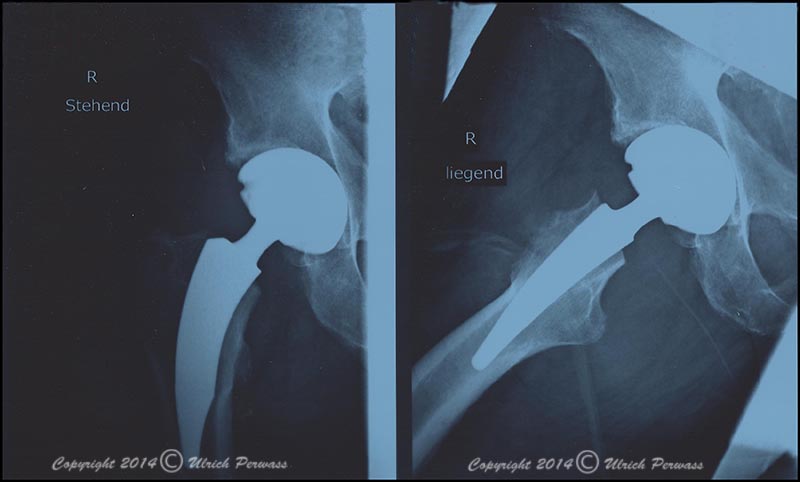

Meine Endoprothese

Hüftimplantat